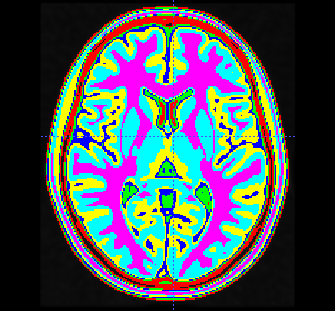

例如,我在3D阵列图像上运行了带有7个类和128个桶的threshold_multiotsu,即尺寸为182x182x218 (磁共振成像分析的标准模板)的1mm分辨率的MNI152 T1-w模板。在我的桌面计算机上,经过的时间大约是3分钟。

基于OTSU方法的7天平分割结果